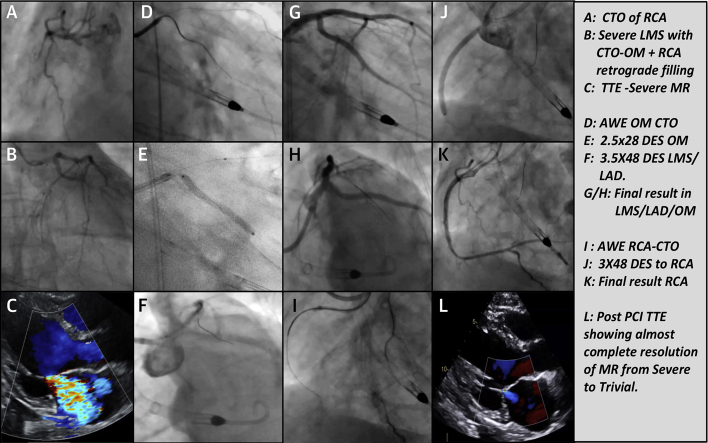

Figure 1.

Original Coronary Angiogram, Echocardiogram (Pre-Procedure and at 6-Month Follow-Up), and Percutaneous Coronary Interventional Procedure Images

(A) Chronic total occlusion (CTO) of the right coronary artery (RCA). (B) Severe left main stem stenosis (LMS) with CTO of the obtuse marginal artery (OM) and RCA retrograde filling. (C) Transthoracic echocardiogram (TTE) showing severe mitral regurgitation (MR). (D) Antegrade wire escalation in CTO of the OM. (E) A 2.5 × 28 mm drug-eluting stent in the OM. (F) A 3.5 × 48 mm drug-eluting stent (DES) in the LMS and left anterior descending coronary artery (LAD). (G and H) Final result in the LMS, LAD, and OM. (I) Antegrade wire escalation in CTO of the LAD. (J) A 3 × 48 mm DES in the RCA. (K) Final result in the RCA. (L) Post-procedural TTE showing almost complete resolution of MR from severe to trivial.